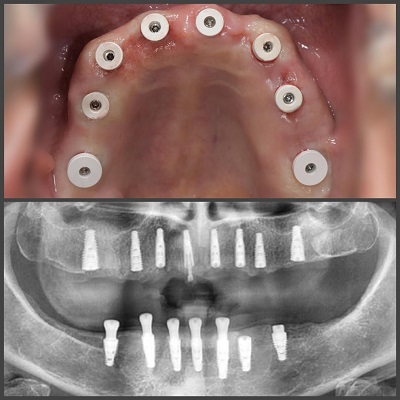

درمانهای جراحی: دندانپزشکان میتوانند برخی از جراحیهای دهانی مانند کشیدن دندانهای آسیبدیده یا دندان عقل، جراحیهای لثه و ایمپلنتهای دندانی را انجام دهند. البته مراجعین بهتر است به بهترین دکتر ایمپلنت در ایران که تخصص بیشتری در حوزه جراحی فک و صورت دارند، مراجعه نمایند.

استفاده از جدیدترین فناوری: بهترین دندانپزشکان با بکارگیری به روزترین تجهیزات و فناوریهای نوین در حوزه دهان و دندان مانند اسکنرهای دیجیتال، رادیوگرافی دیجیتال و… در تلاش اند تا بهترین خدمات را به بیماران ارائه دهند.

- ایمپلنت دیجیتال